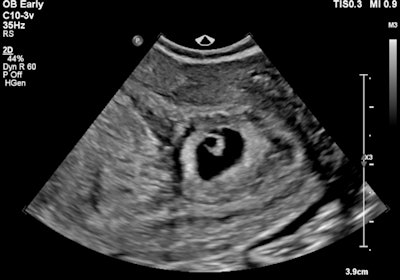

Transvaginal ultrasound in transverse orientation. The left adnexal mass demonstrates a hyperechoic tubal ring sign (blue arrows). The uterus (red arrows) demonstrates a double decidual reaction.The patient decided to have an outpatient surgical termination of the intrauterine pregnancy. A follow-up ultrasound was performed two days post termination due to increasing abdominal pain. A round, thick-walled avascular structure with a central hypoechoic component was seen within the left adnexa. It featured a hyperechoic rim consistent with a tubal ring sign. However, the left ovary was not identified. A moderate volume hemoperitoneum was also seen.